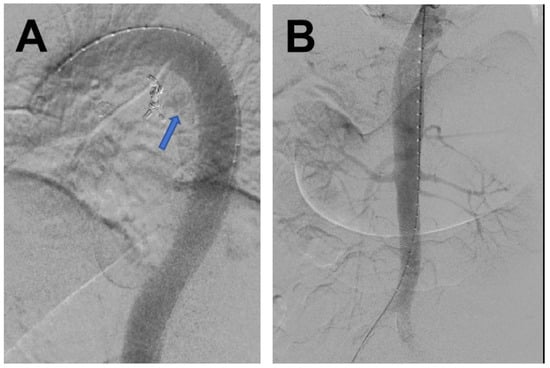

2. Case Report